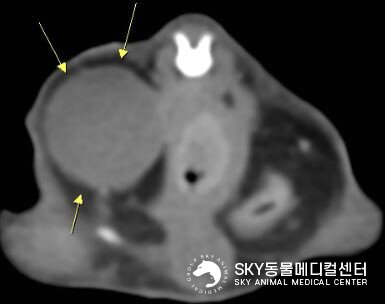

본문 이미지 - CT 검사에서 방광 탈장이 확인된 모습(스카이동물메디컬센터 제공) ⓒ 뉴스1

CT 검사에서 방광 탈장이 확인된 모습(스카이동물메디컬센터 제공) ⓒ 뉴스1